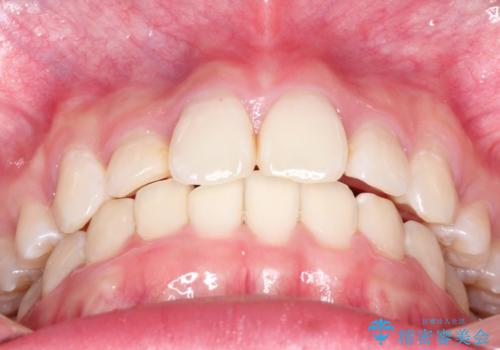

- 20代女性

- 上顎の両側第1小臼歯抜歯による抜歯矯正を計画した。

上顎の抜歯により上の前歯の位置を大幅に後ろに下げることができます。

奥歯の位置関係など、様々な要素を加味し、適応を判断する必要があります。